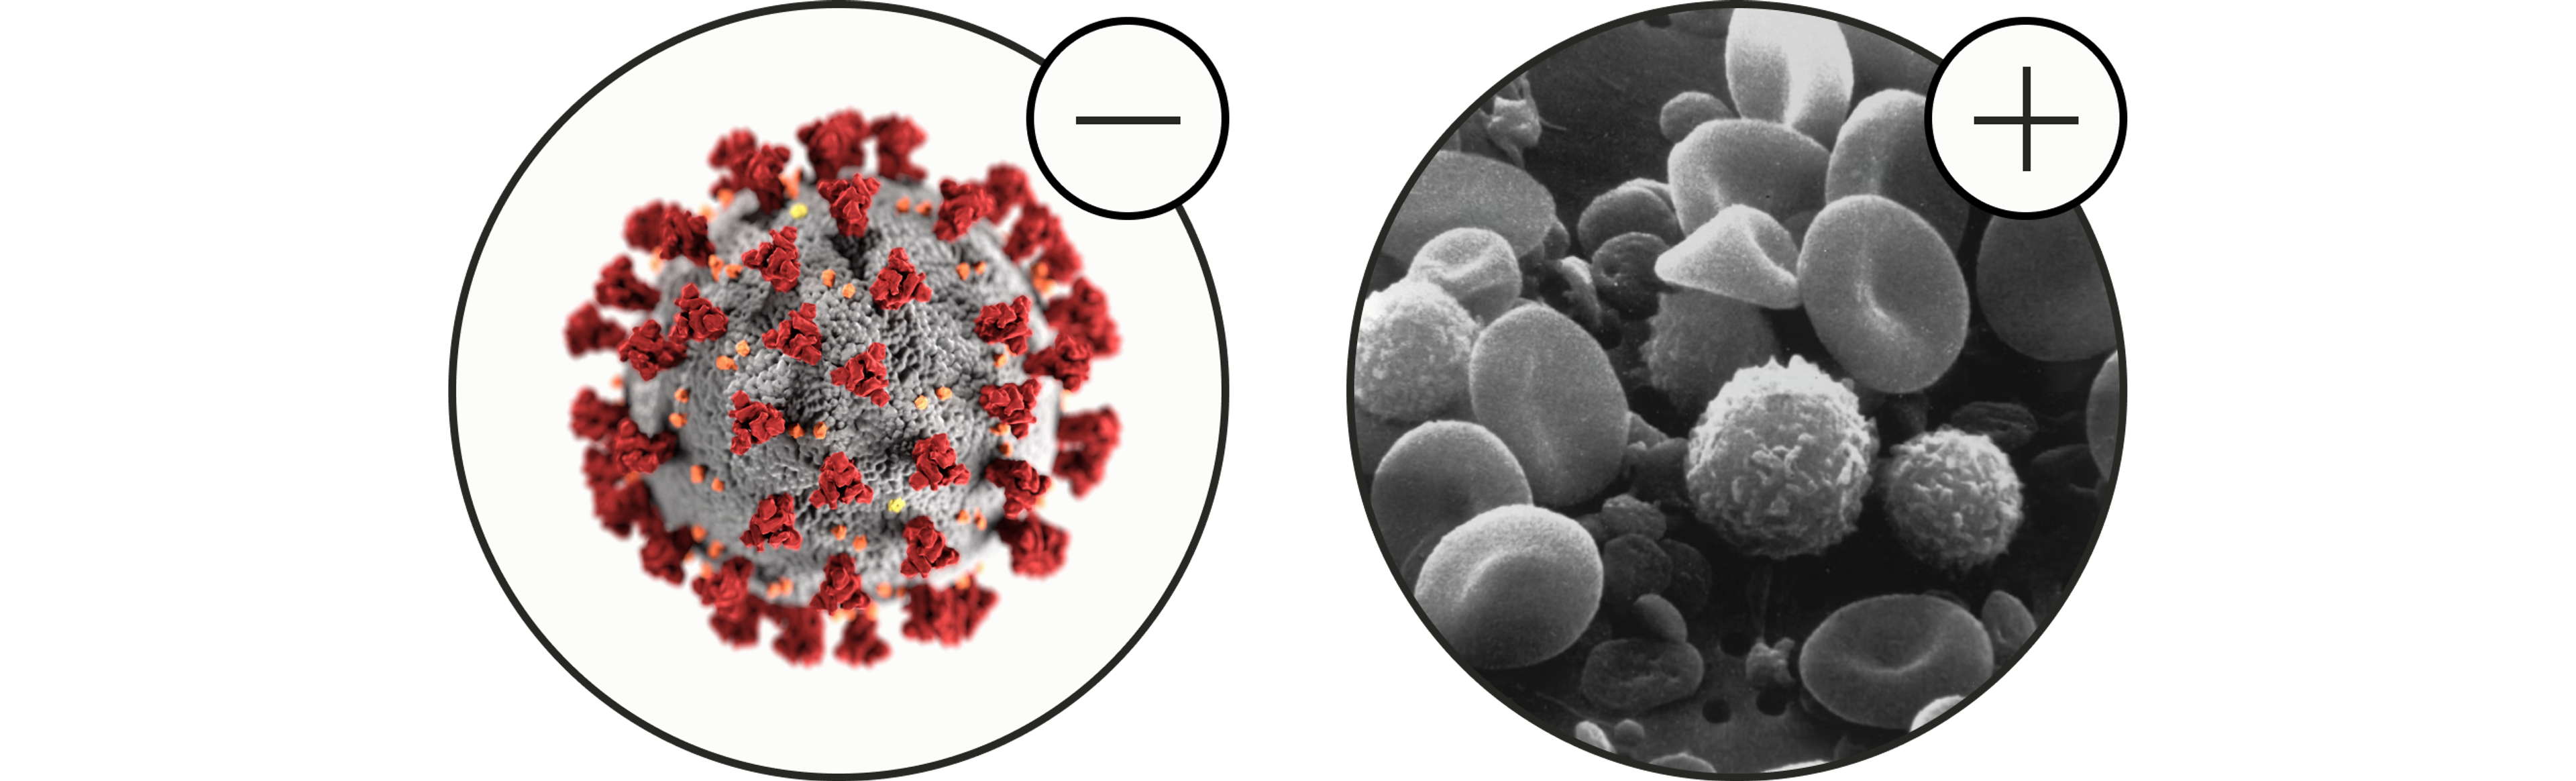

2. Regulates the immune system

Autophagy has emerged as a pivotal player in the body's immune response, aiding in the removal of pathogens and enhancing the performance of immune-active cells. It acts as a strong form of defense against invaders.[3]